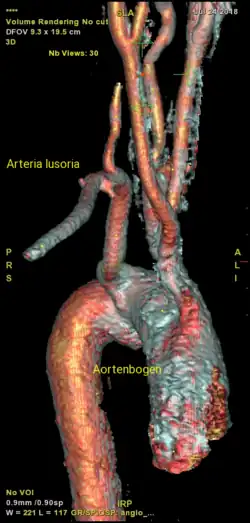

Arteria lusoria

Bei der Arteria lusoria (lat. lusorius: Spiel...) handelt es sich um einen atypischen Verlauf der Arteria subclavia dextra (rechte Unterschlüsselbeinarterie), siehe auch Kiemenbogenarterie (Vierter Kiemenbogen). Diese entspringt statt aus dem Truncus brachiocephalicus (Arm-Kopf-Gefäßstamm, rechts) aus dem Arcus aortae (Aortenbogen) und verläuft hinter, selten vor der Speiseröhre nach rechts zu ihrem Versorgungsgebiet. Typischerweise ist diese Fehlbildung mit einem atypischen Verlauf des Stimmbandnerven verbunden.

Typisches Bild einer Arteria lusoria in der Computertomographie. (1) Luftröhre, (2) Speiseröhre, dahinter (3) A. lusoria aus dem Aortenbogen entspringend.

Typisches Bild einer Arteria lusoria in der Computertomographie. (1) Luftröhre, (2) Speiseröhre, dahinter (3) A. lusoria aus dem Aortenbogen entspringend. -